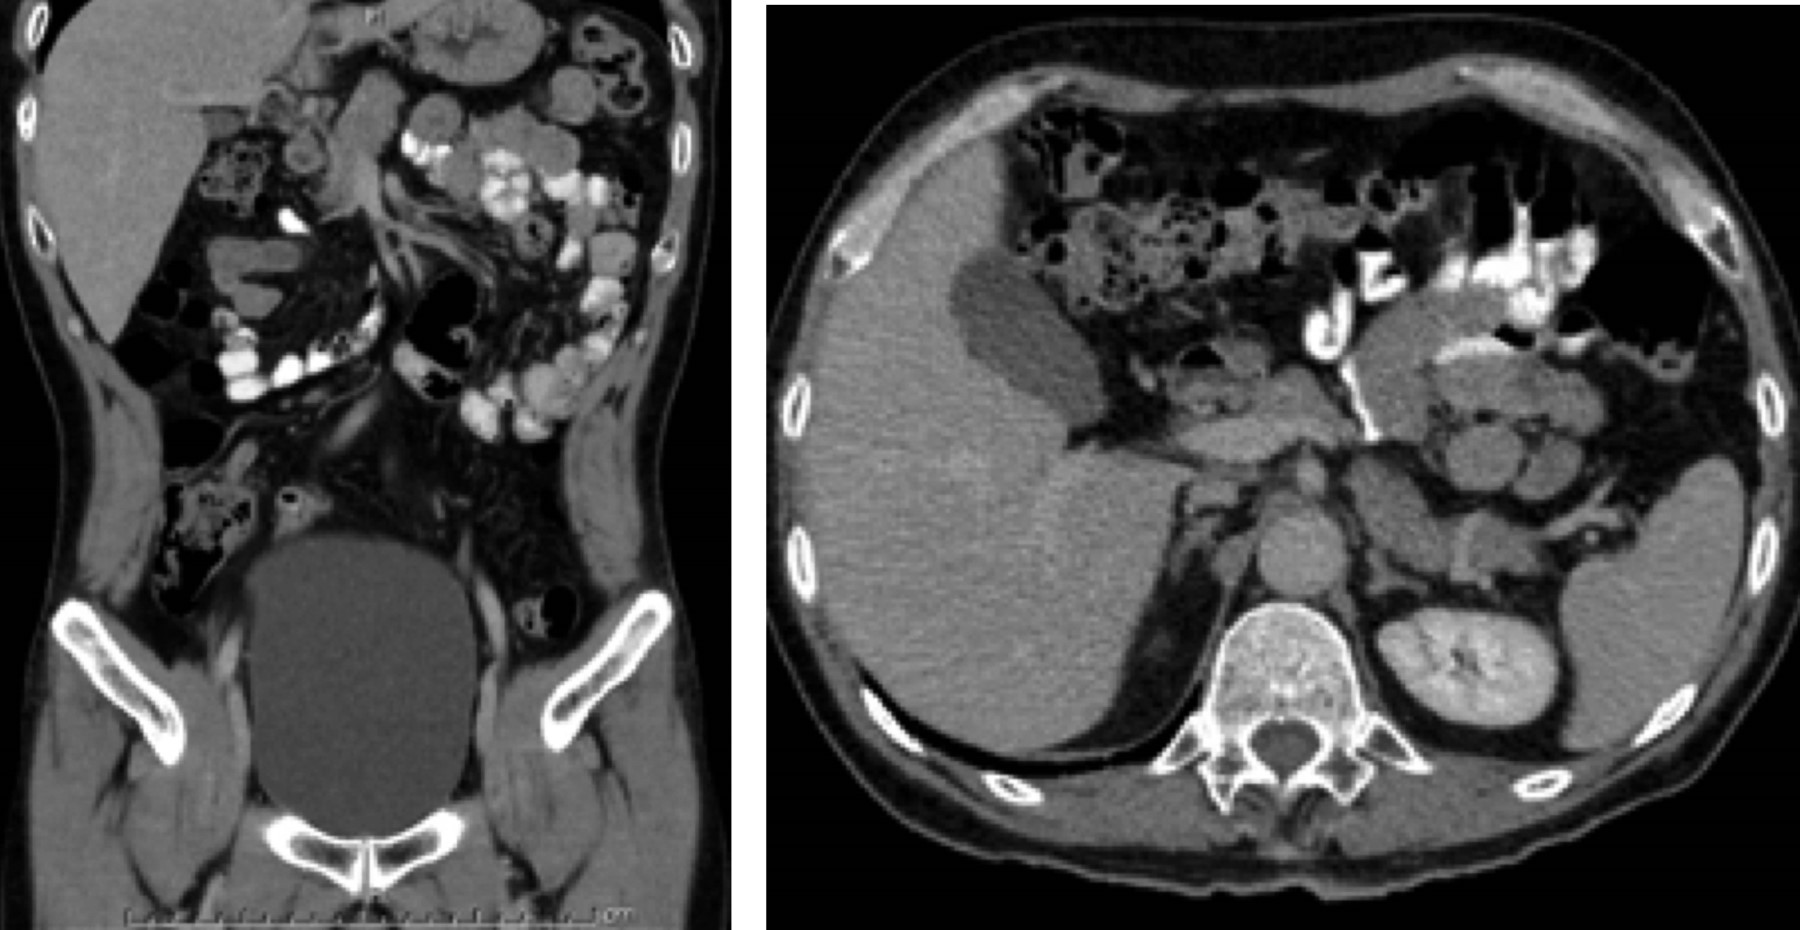

Se realiza estudio de imagen tomografía axial computarizada con doble contraste (oral e intravenoso), donde se observa conglomerado de asas de yeyuno en cuadrante superior izquierdo, cerca del ligamento de Treitz, sin paso del medio de contraste hacia el íleon, sugerente de hernia interna (Figura 1).

Figura 1